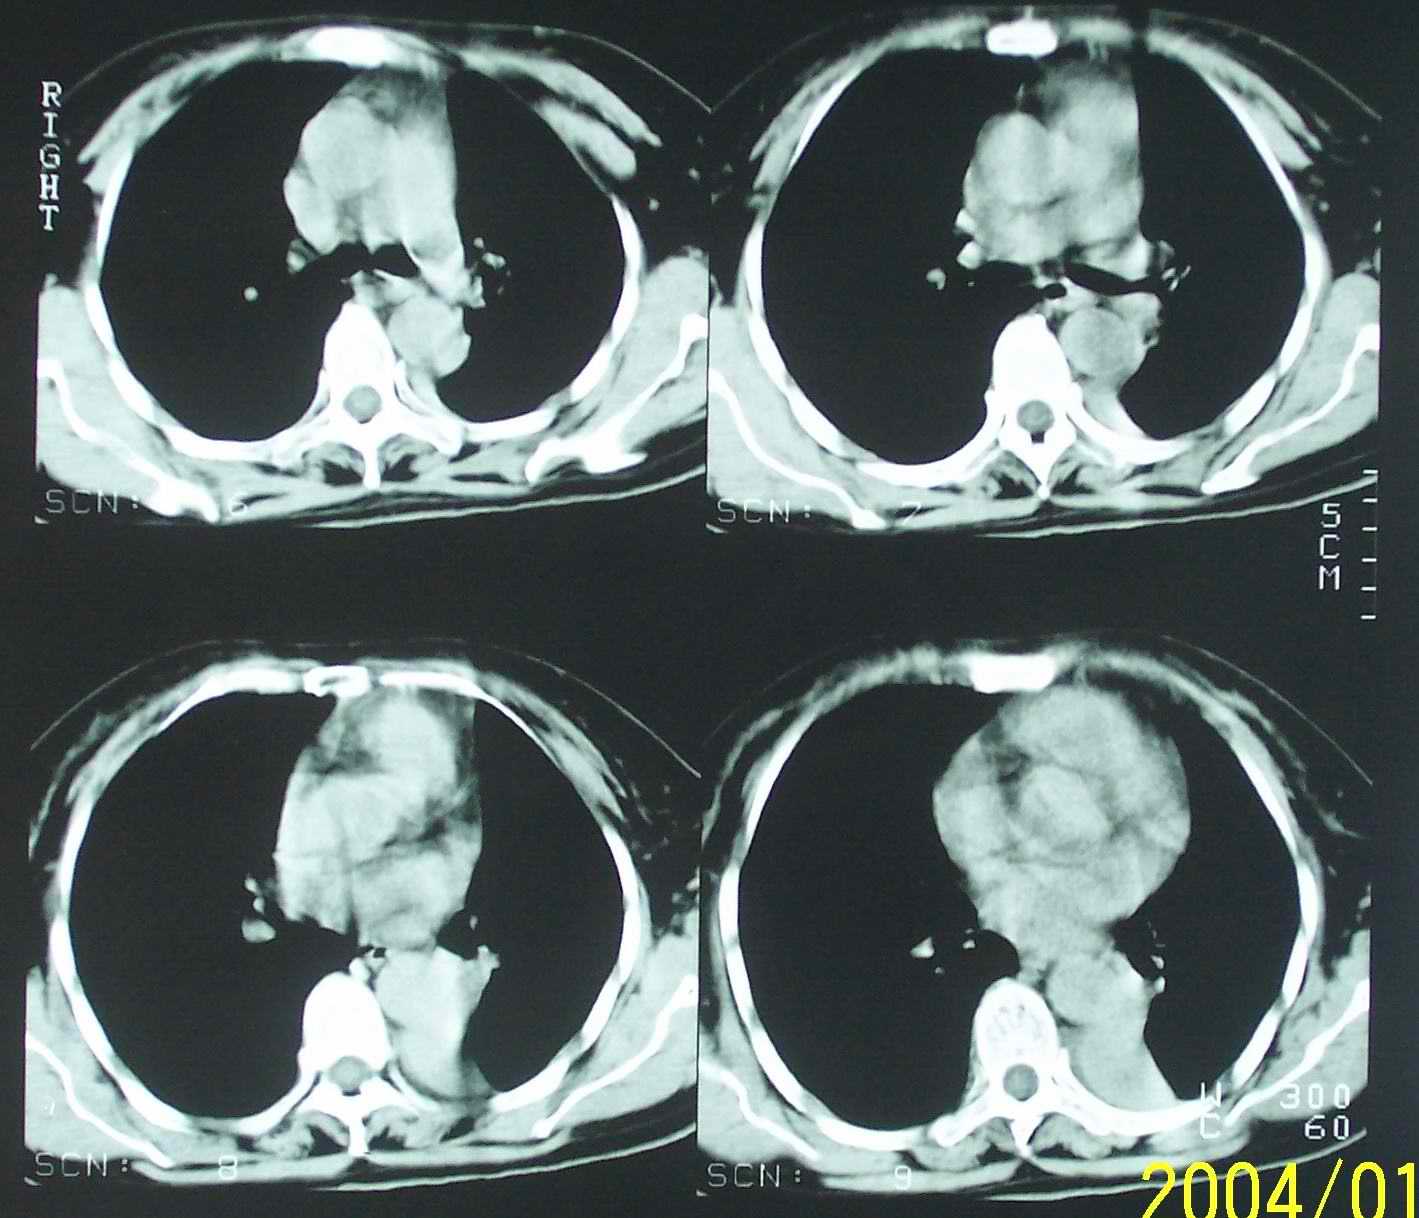

53岁女性,间断性腰部困疼、乏力一年,活动时加重。

1.左侧胸腔无明显萎陷,肺体积缩小,含气量减少,纵隔心脏左移。从这个意义来讲,左下肺病灶应该首先考虑肺不张。

2.左下肺病灶密度太过均匀,边缘过于光整锐利,位置特殊,其次应该考虑隔离肺的可能。

3.连续观察不能完全否定病灶是疝入胸腔的脾脏(扫描不怎么规范,跨越过大),所以膈疝也需要考虑。

应该是脾脏,因此是膈疝,

从连续观察的层面看象是疝入的脾脏

补充一下病史:三天前因咳嗽咳血检查胸片见左下肺索条状影,后复查ct